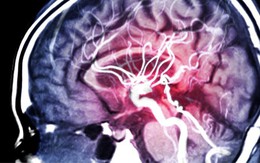

Phát hiện gây sốc: Huyết áp chưa tăng nhưng não đã lão hóa

Tăng huyết áp là nguy cơ hàng đầu của đột quỵ và sa sút trí tuệ, nhưng tổn thương não có thể bắt đầu từ rất sớm, thậm chí trước khi huyết áp có dấu hiệu tăng. Phát hiện này mở ra cách hiểu hoàn toàn mới về sự liên quan giữa huyết áp và sức khỏe não.

Đột quỵ tái phát rất nguy hiểm, phòng ngừa ra sao?

Đột quỵ là tình trạng nguy cấp đe dọa tính mạng và để lại di chứng nặng nề. Nhưng đột quỵ tái phát còn nguy hiểm hơn.